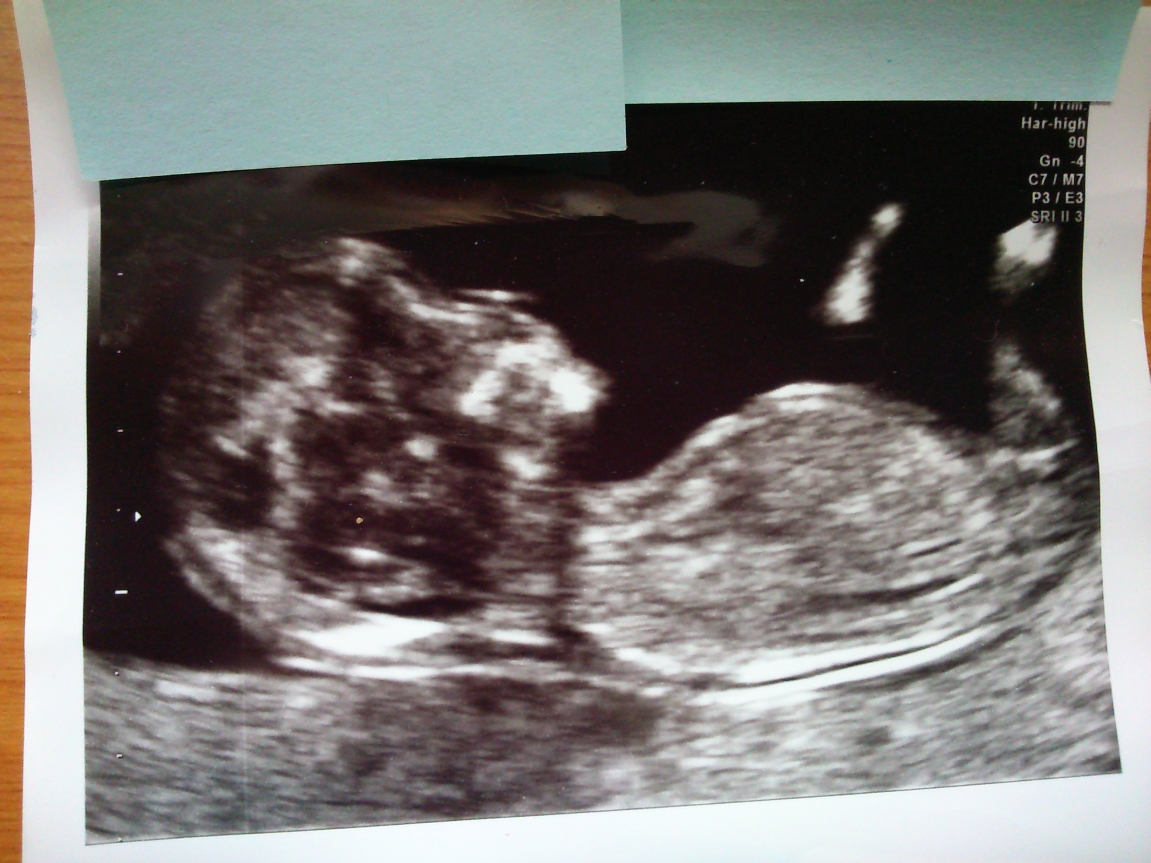

Nub shot at almost 13 weeks, can you have a guess for me please?

I hope these shots come out on the computer as clear as the photos I have in my hand. They are from my 13 week scan. Although officially dating at 13 weeks, a number of factors make me think I was actually closer to 12-12.5 weeks. I am now nearly full term.

We opted not to find out the sex at 20 weeks, but now I am torturing myself and wishing we had. Not that I have long to find out, hahaha! I've not been able to work it out from looking at pretty much every nub picture and tutorial on the internet, but hoping you folks can take a guess - I will update after the birth, promise.